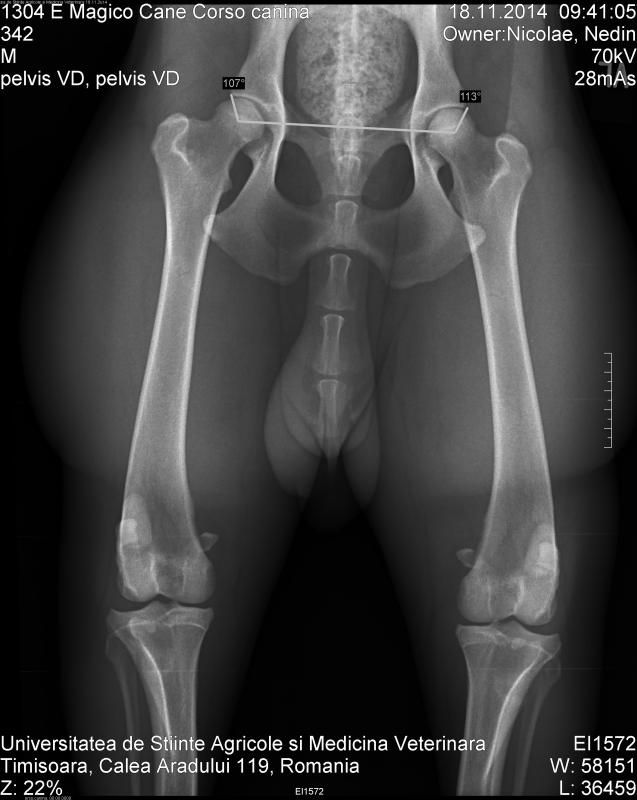

En wat vinden jullie van de heupfoto's?

Heb ze ook al doorgestuurd naar Maarten Kapen, maar ben ook benieuwd naar jullie mening